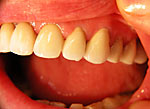

Die folgenden Patientenfälle sollen Ihnen einen Einblick in die Möglichkeiten der modernen Implantation geben.

Implantation – Patientenbeispiel 2: